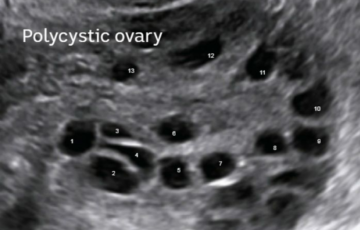

• PCOS: Shkaqet, Simptomat dhe Mundësitë e Trajtimeve për Menaxhimin e Sindromës ...